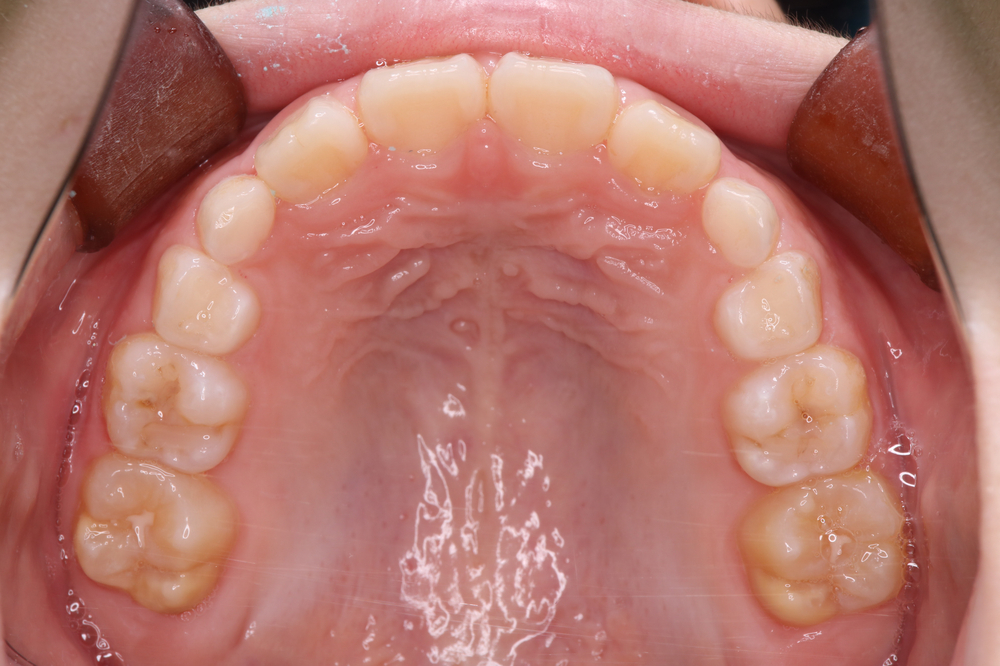

【上の歯】